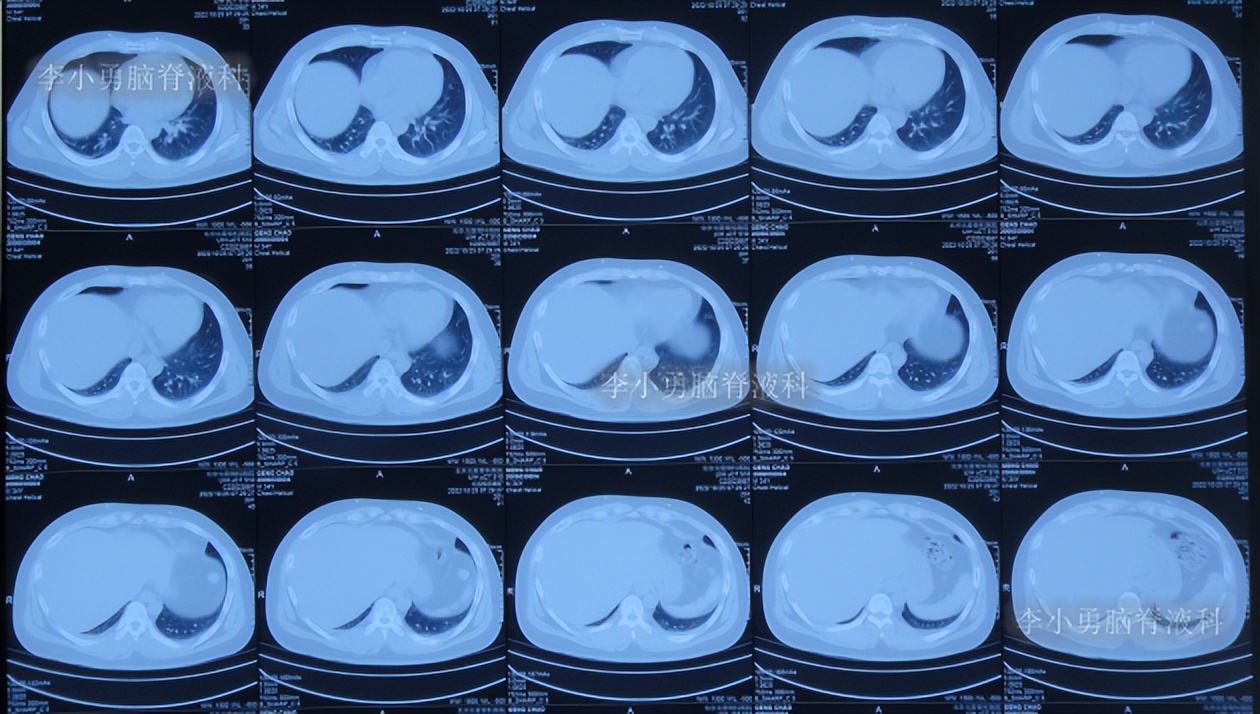

半月后即2022年6月17日,第3次住入李小勇脑脊液科,入院时:进食差,言语混乱,记忆力差,行走差(图-52);查头颅CT示右侧颞角增大,四脑室也稍大(图-53);肺部CT有感染(图-54)。

图-54:肺部CT